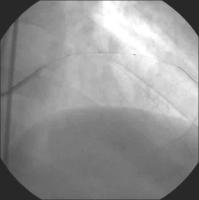

Linke Koronararterie LAO/Kaudalprojektion

Abbildung 2

Keywords: Arteria coronaria sinistraKardiologieKoronarangiographie